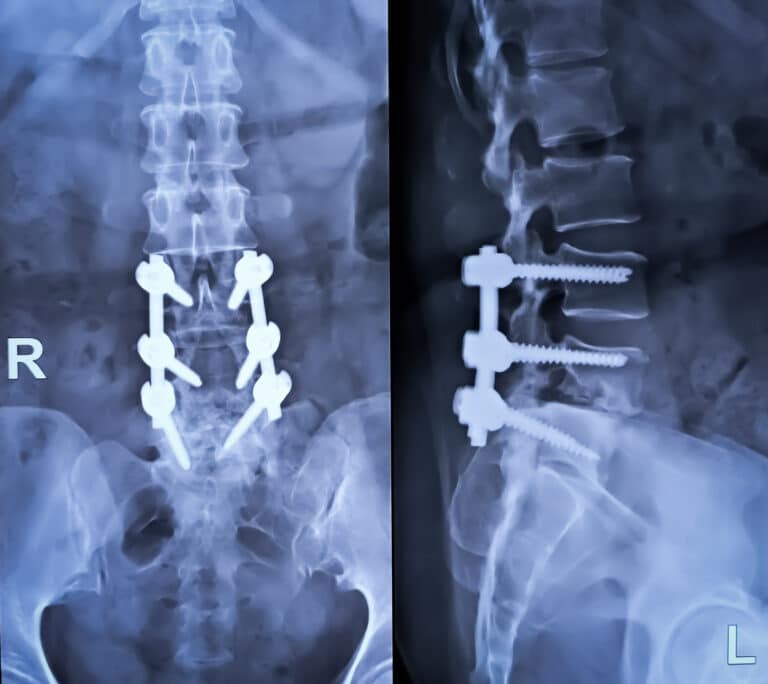

- The surgeon inserts titanium plates, rods, and screws to anchor the vertebrae.